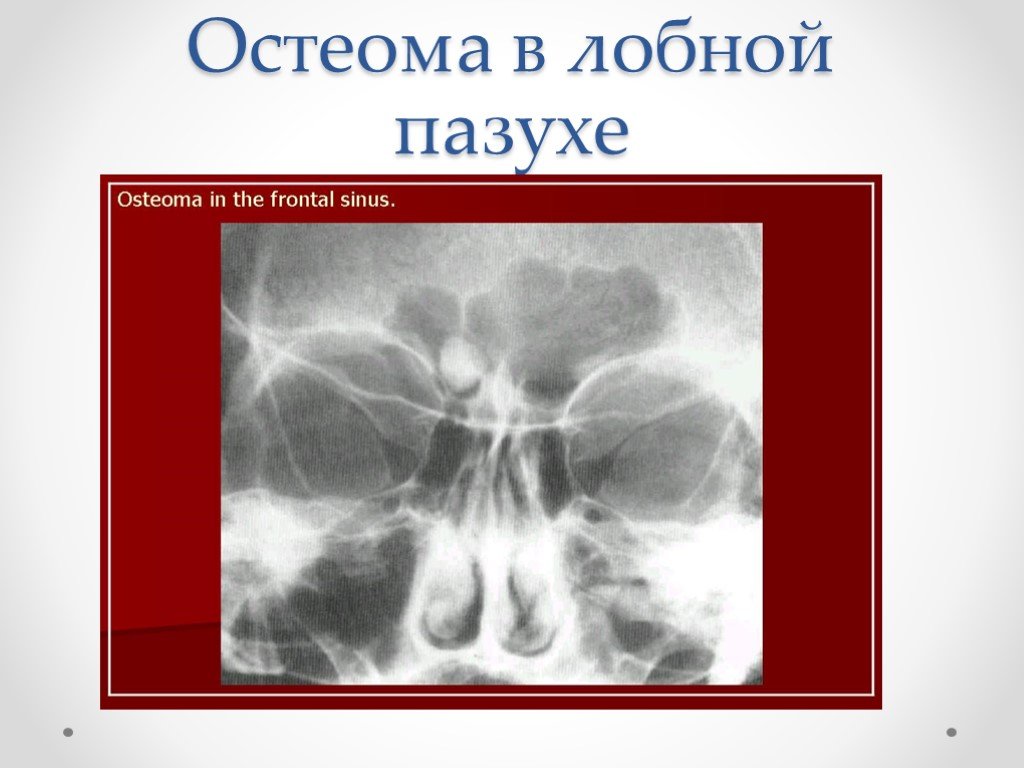

Остеома лобной пазухи

Остеома лобной пазухи